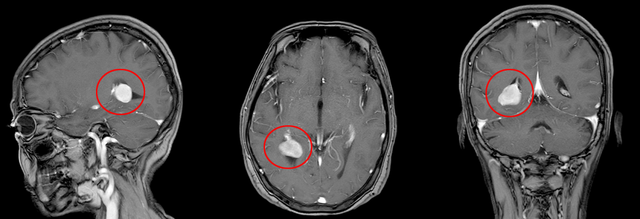

▲患者头颅MR增强

考虑脑膜瘤可能!

入院后,神经外科主任王文华立刻组织术前讨论并表示:该患者肿瘤位于三角区,位置较深,肿瘤大小2.2cm*1.6cm,肿瘤周围血管、神经丰富,手术难度较大,传统开颅肿瘤切除术中出血多,肿瘤定位困难,对血管神经的破坏较大。市中医医院引进的术中导航系统可以精准定位肿瘤,计算最优路径,减少脑组织的损伤,减少术中出血。